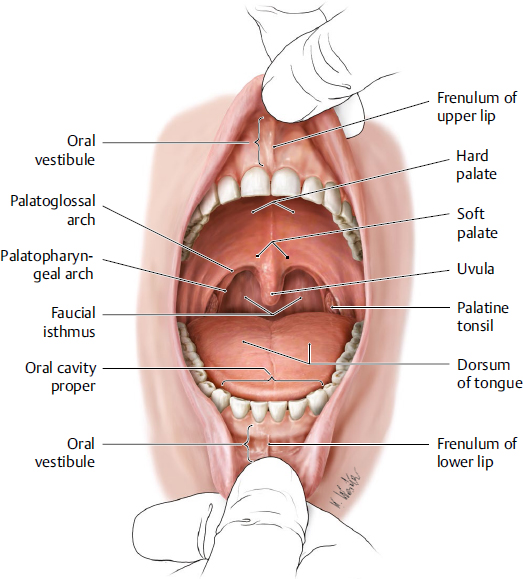

what are the divisions of the pharynx

regions of the pharynx

nasopharynx

oropharynx

laryngopharynx

nasopharynx: borders

nasopharynx

extends from behind the nose/ nasal cavities

to the soft palate

nasopharynx: which tract is it a part of

the nasopharynx is a functional part of the respiratory tract

oropharynx: borders

oropharynx

from below the soft palate

to the tip of the epiglottis

laryngopharynx: borders

laryngopharynx

from the tip of the epiglottis

to the lower border of the cricoid cartilage

laryngopharynx: at which vertebrae is the cricoid cartilage level with

the cricoid cartilage lies at the level of C6

laryngopharynx: what structure is anterior to it

the entire length of the larynx

laryngopharynx: what structure is it continuous with

the laryngopharynx is continuous with the oesophagus

laryngopharynx: at which vertebrae is it level with posteriorly

the laryngopharynx extends posteriorly from the third to the sixth cervical vertebrae